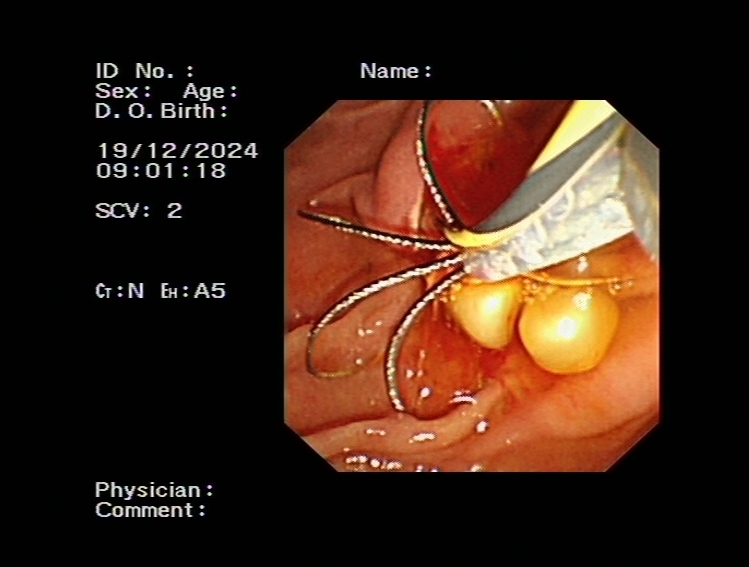

ERCP(內(nèi)鏡逆行胰膽管造影術(shù))是膽胰疾病精準(zhǔn)內(nèi)鏡診療技術(shù),具有不開(kāi)腹、風(fēng)險(xiǎn)小、創(chuàng)傷小、恢復(fù)快、住院時(shí)間大大縮短的優(yōu)點(diǎn),尤其是對(duì)年齡大、體弱多病的患者尤為適宜。ERCP主要運(yùn)用于膽總管結(jié)石的取出,以及在經(jīng)口膽道子鏡的輔助下完成肝內(nèi)膽管結(jié)石的取出。

0b4174cdbf1f4e508687f388367c9ca6.Jpeg

bc72d6558d394d8ea787e762f054a7c5.Jpeg74bcac877ae44a9da8e58dab53d178ee.Jpeg75e90c629e6545de9ee764d5e15bc91e.JpegERCP取出膽總管結(jié)石